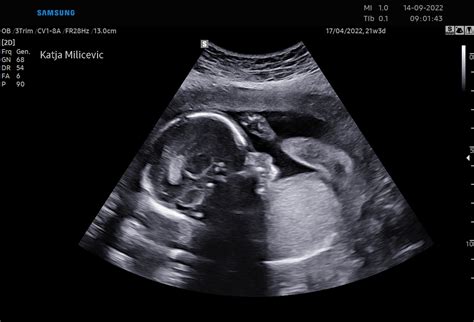

Otrokovi sklepi in mišice bi morali biti anatomsko pravilno razporejeni. Njegov živčni sistem že zaznava dražljaje iz okolja, na primer, ko položite roko na trebuh. Kolcanje je še ena oblika navajanja na življenje zunaj maternice. Za uravnavanje respiratornega sistema otrok že med nosečnostjo vadi dihanje s požiranjem plodovnice, ki jo nato izloči s pomočjo prepon. Ta pojav je jasno viden na ultrazvoku, kjer starši pogosto doživijo čustven trenutek ob pogledu na otroka s palcem v ustih in kolcanjem njegovega majhnega telesa.

Nadaljnje pomembno obdobje za preglede je med 20. in 22. tednom nosečnosti. Takrat se opravi natančen ultrazvočni pregled morfologije ploda, kjer se preveri lega ploda, količina plodovnice, lega posteljice, žile v popkovnici, izmeri se rast in teža ploda ter pregledajo vsi organi, kar omogoča odkrivanje večine večjih napak pri plodu. Zakonodaja sicer omogoča dva ultrazvoka pri normalni nosečnosti: enega v zgodnji nosečnosti in drugega med 20. in 22. tednom. Kasneje se rast ploda spremlja z merjenjem razdalje med sramno kostjo in vrhom maternice.